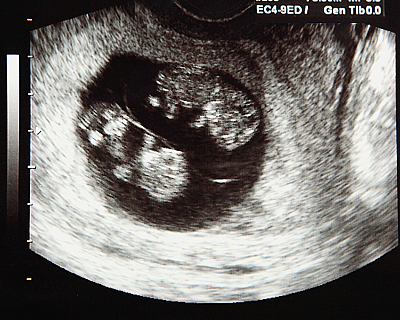

Многоплодная беременность

Беременность двойней — редкий и в то же время удивительный опыт. Она может быть радостной, тревожной и физически сложной. С двумя малышами внутри вам предстоит особый путь, где всё — от ранних симптомов до родов — происходит чуть раньше и чувствуется сильнее.

Причем в утробе у девочек-близнецов тоже была был очень редкий расклад.